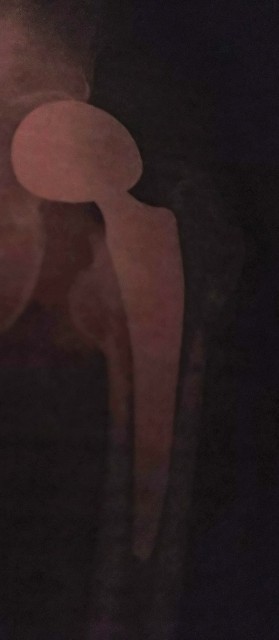

ゴリゴリ感消退の原因

整形外科のDr.の説明で分かりました。前述した様に、人工物は大腿骨頭から、削除。では何がゴリゴリ感をとってくれたのか。人工物をとり除いたあとの空間に抗生物質等含んだ物資が蓄積し、それが効いたのでしょう。でした。